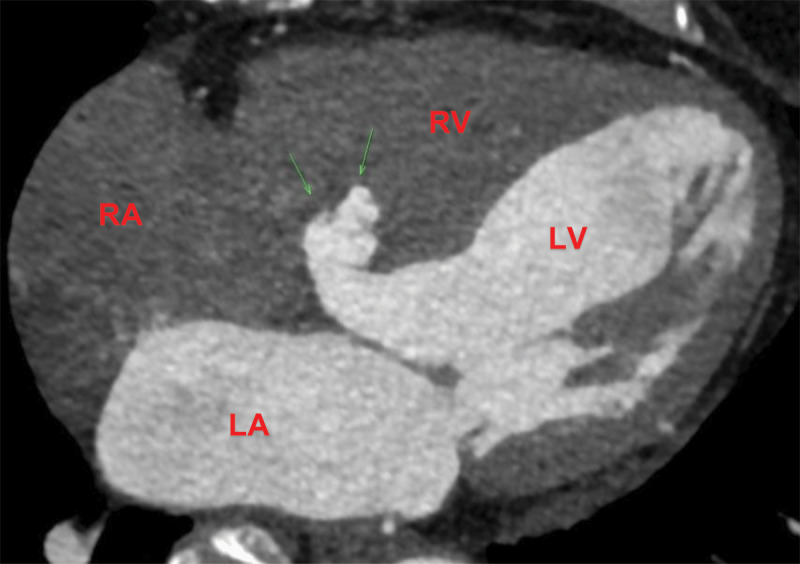

We present a case of a 75-year-old female with a history of idiopathic small fiber neuropathy, essential hypertension, and heterozygous familial hypercholesterolemia who was evaluated for exertional dyspnea and fatigue. Coronary computed tomography angiography demonstrated a 16-mm wide-neck windsock aneurysm of the interventricular septum along with a patent foramen ovale and left-to-right shunting. This case underscores the role of advanced cardiac imaging in detecting rare structural abnormalities.